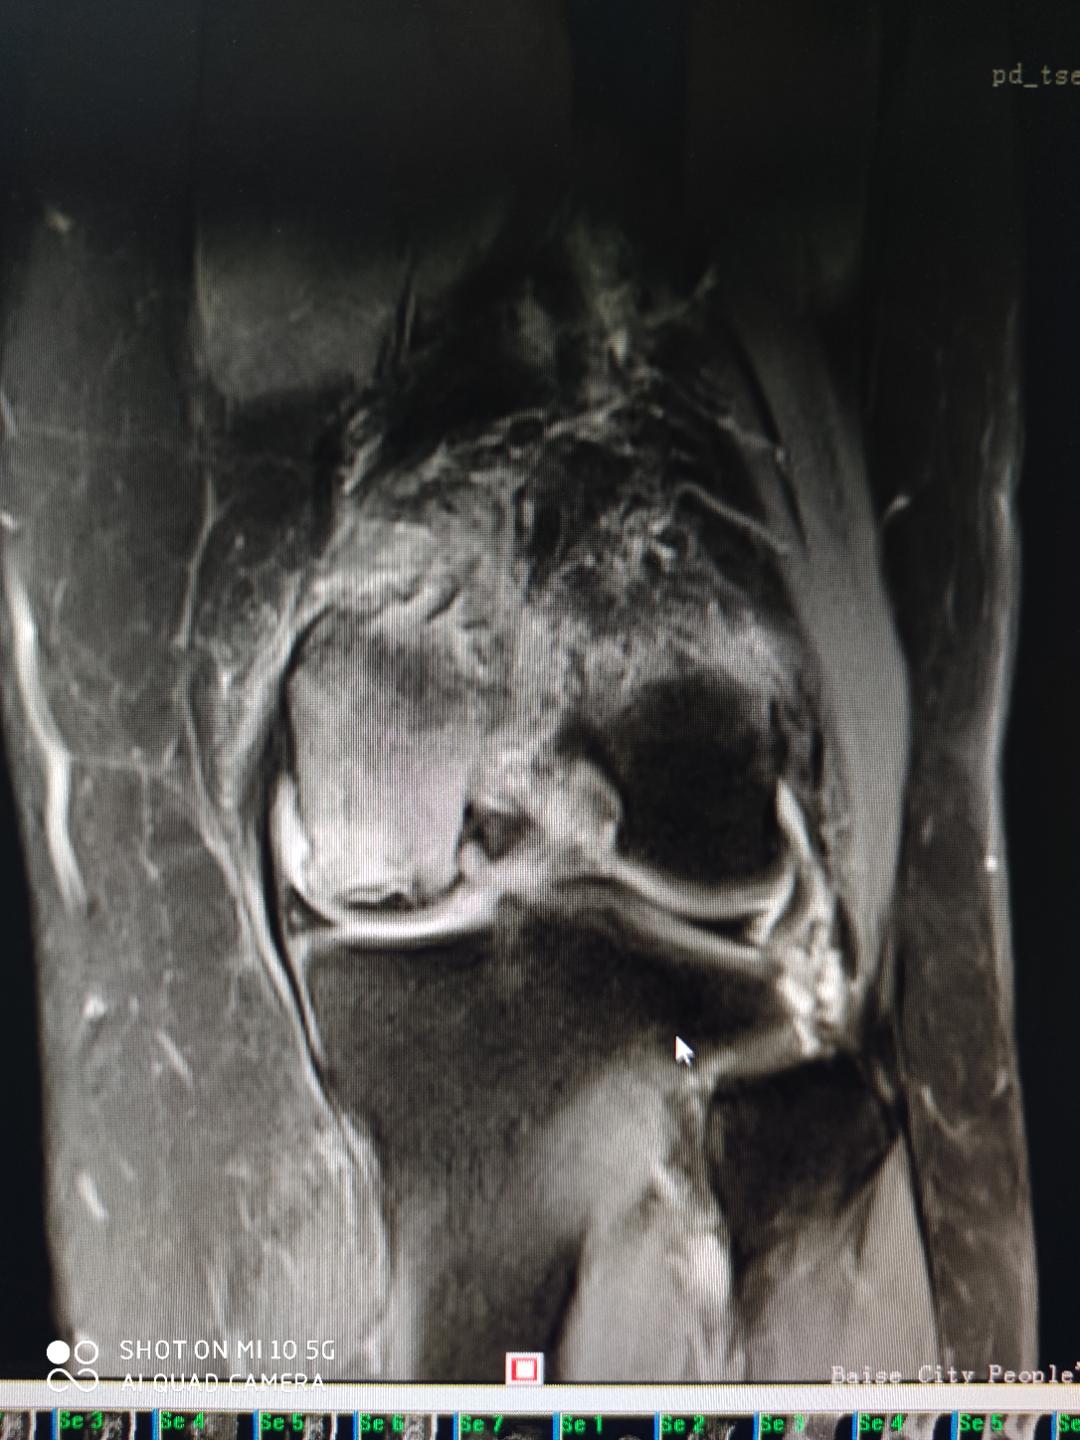

患者张女士,58岁,因左膝关节疼痛1年余,加重4个月后到百色市人民医院关节外科住院。患者告知,其左膝疼痛严重,白天及夜间疼痛明显,活动时加重,严重影响生活及日常工作。她曾在外院多次治疗,但是无明显效果,至今左下肢无法负重行走,经熟人介绍后,到百色市人民医院门诊就诊,诊断为“左股骨远端自发性骨坏死”而收住医院关节外科。

术前